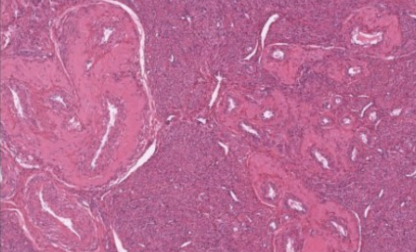

label this slide

ampulla of oviduct